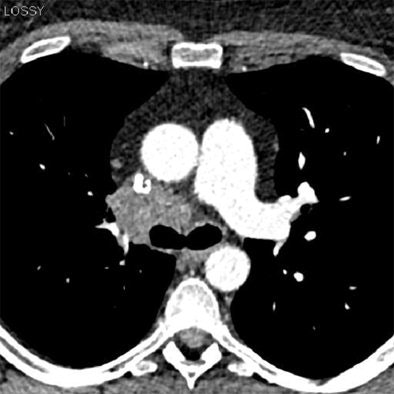

In their study, Dr. Richard A.P. Takx, and colleagues from Maastricht University Medical Center in the Netherlands, along with investigators from the Medical University of South Carolina and two other centers, compared image noise between the raw-data-based reconstruction algorithm and traditional FBP. The study examined 20 consecutive patients who underwent coronary CT angiography using the pECGdual_step scan protocol.

"Second-generation DSCT hardware provides a prospective dual-step ECG pulsing (pECGdual_step) protocol in which adaptive prospective ECG-triggered cCTA acquisitions are combined with ECG-gated tube current modulation," Takx wrote in an email to AuntMinnieEurope.com. "Specifically, full tube current is triggered to a limited portion of the cardiac cycle (e.g., at 30% or 70% of R-R) for coronary artery analysis while low-radiation tube current (20% mAs) is applied during the majority of the cardiac cycle (e.g., 10-90% R-R), thus providing the reduced dose features of prospective triggering while obtaining a functional image series."

Takx and colleagues reconstructed the images using regular FBP at full-dose (Group 1a) and low-dose (Group 1b) and with SAFIRE with five iterations at low-dose (Group 2). They evaluated three regions of interest (ROI) for signal intensity, image noise, signal-to-noise-ratio (SNR) and contrast-to-noise-ratio (CNR). Finally, they evaluated subjective image quality on a four-point scale based on image sharpness and noise.

"Our objective was to compare objective and subjective image quality parameters using SAFIRE versus conventional FBP reconstructions in patients who underwent low-dose CCTA (coronary CT angiography)," Takx noted.

Objective image noise was reduced by an average of 22 % (P < 0.0001) in Group 2 compared to Group 1b. There was also a significant (P = 0.0156) improvement in overall subjective image quality in Group 2 compared to Group 1a.

Iterative reconstruction enabled significant reduction in image noise without loss of diagnostic information, and has the potential to improve image quality in low-dose functional CCTA and possibly reduce radiation dose even further, the group concluded.

"DSCT (dual-source CT) still remains sensitive to motion artifacts, especially in patients with arrhythmia," Takx stated. "In case of a motion artifact the images acquired in the low dose ECG-pulsing window can potentially be used for evaluation of coronary patency. However, these low dose FBP reconstructions contain a high level of image noise. In our study we demonstrate that low-dose CCTA reconstructed with the SAFIRE algorithm resulted in significant reductions in image noise and significant improvements in objective (SNR and CNR) and subjective image quality compared to low-dose FBP reconstructions."